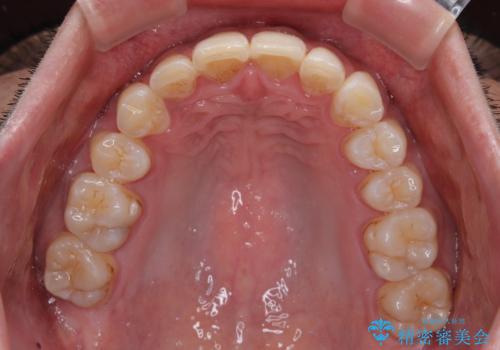

- 深い咬み合わせと前歯のデコボコを改善したいとのことで来院された患者様です。

口元の突出感はないものの、上顎前歯のデコボコが著しく、右側の咬み合わせがずれていたため、上顎右側第一小臼歯1本を抜歯することとしました。

咬合力が非常に強く、抜歯したスペースがなかなか閉じないであろうことは予想できましたが、思っていた以上に期間がかかりました。

前歯のすり減りも著しかったため、仕上げの位置の調整にも期間を要しました。